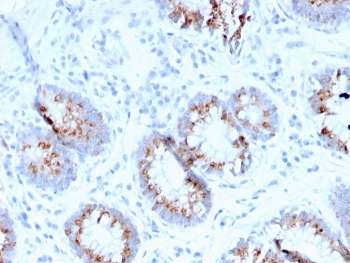

IHC staining of FFPE human colon carcinoma with MerTK antibody (clone TPKR-1). HIER: boil tissue sections in pH9 10mM Tris with 1mM EDTA for 10-20 min and allow to cool before testing.